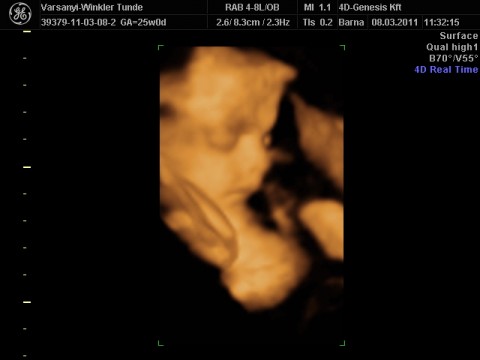

Nagyon édes a kis kukacosod, s látom beindult most már teljesen a nagy bevásárlás nálad is!